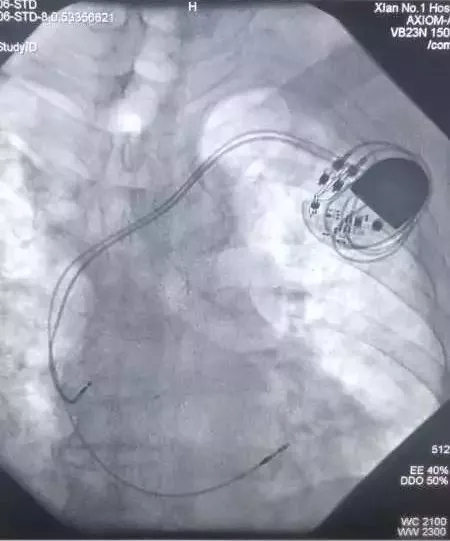

CCU成功实施男同视频 首例双主动电极抗核磁起搏器植入术